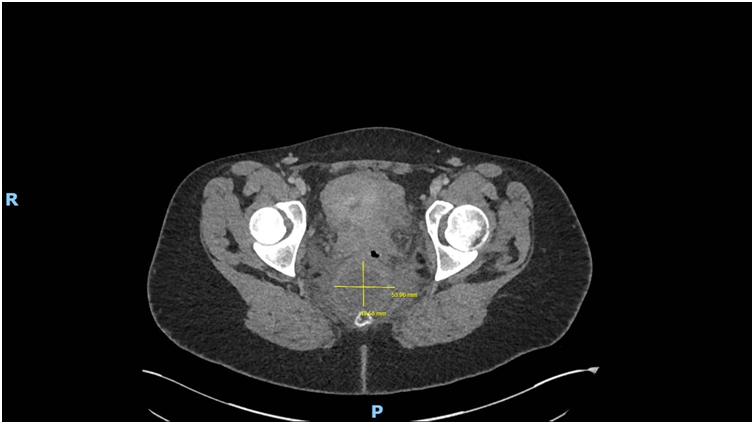

Imaging via MRI and CT demonstrated a complex, encapsulated lesion with peripheral enhancement and restricted diffusion. Multidisciplinary evaluation suggested a congenital epidermoid or duplication cyst. Given the absence of malignancy and surgical complexity, a conservative management strategy was adopted.

Figure 5: Figure 5 Duplication cyst axial 2020 plane post cystic aspiration

Figure 8: Figure 8 Duplication cyst 2020 axial plane